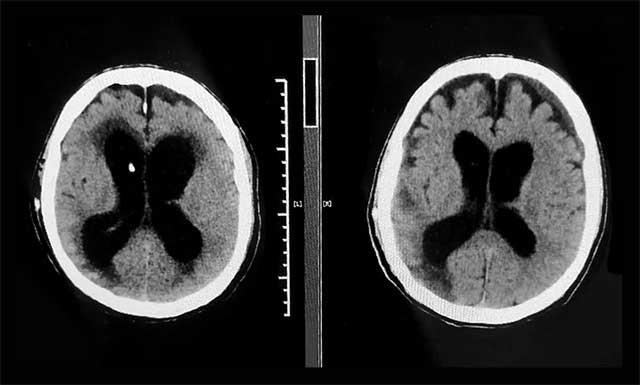

▲ 术前(左)和出院前(右)CT比对,患者原先扩张的脑室已缩小,症状改善明显

入院时,汪先生神志昏迷、气管切开无法自主呼吸、鼻饲饮食、留置尿管,可以说处于“植物人”状态。像这样的脑出血昏迷患者,病情随时可能恶化,张琪博士团队为患者完善相关检查,结合既往病史,多次开展病情讨论评估,制定了有针对性的治疗方案。鉴于患者有中度脑积水,严重影响意识恢复,张琪博士亲自为患者进行了脑室-腹腔分流手术。